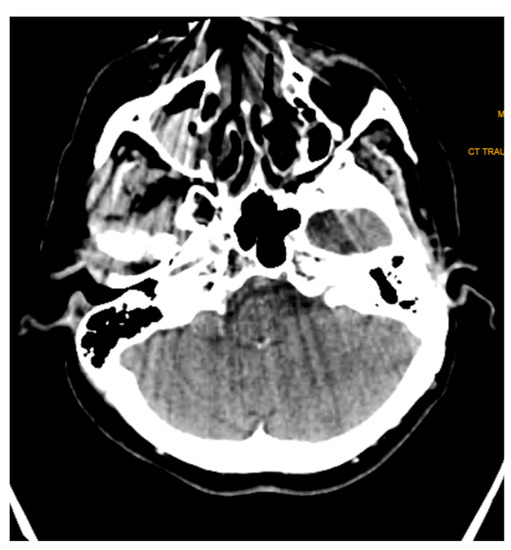

A similar example is presented in the T2 axial section (Figure 9). The porcelain fused to metal fixed prosthesis placed in the mandibular anterior teeth caused a no-signal, presenting anterior artifact extending to the level of the maxillary teeth. This is a particularly inconvenient problem since the MRI imaging was performed to check for any malignant spread in a recurring cancer patient. Although different technical alterations gave us a clue about the region in one plane, it was not sufficient.

Figure 9. T2 weighted image—axial section showing loss of signal in anterior mandible and maxilla due to metal fused crown in mandibular anterior. This obscures the purpose of the MRI, which was performed to identify any malignant spread in a recurring cancer patient.